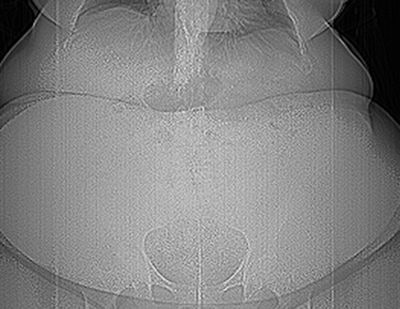

Reading the images can be difficult, especially in the postoperative period, due to bad contrast for these large patients with a water-soluble contrast material, dilatation of the esophagus, size of the neo pouch, permeability of the anastomosis, and opacification of the initial small bowel. A CT exam should be performed when an upper GI contrast study has failed in a suspected case of fistula, and it can also rule out other complications.

In an e-poster presented at ESGAR 2013, Dr. Rajeev Suri, an associate professor of vascular and interventional radiology at the University of Texas Health Science Center in San Antonio, U.S., elaborated on the logistical difficulties posed by the growing obesity epidemic. These include the weight limits and aperture diameters of imaging equipment, scheduling and transport issues, working out how well the patient will fit in the imaging equipment, and modification of equipment settings to optimize image quality for the obese patient.

"Current imaging technology is limited in providing the desired quality of imaging in obese patients," he wrote. "Radiologists and technologists need to be aware of the limitations of imaging equipment and the equipment adjustments that can be made to improve image quality in obese patients. Best technique depends MORE on weight limit and aperture sizes THAN the appropriateness of the exam. Consider portable radiography or sonography equipment for patients who cannot be transported."